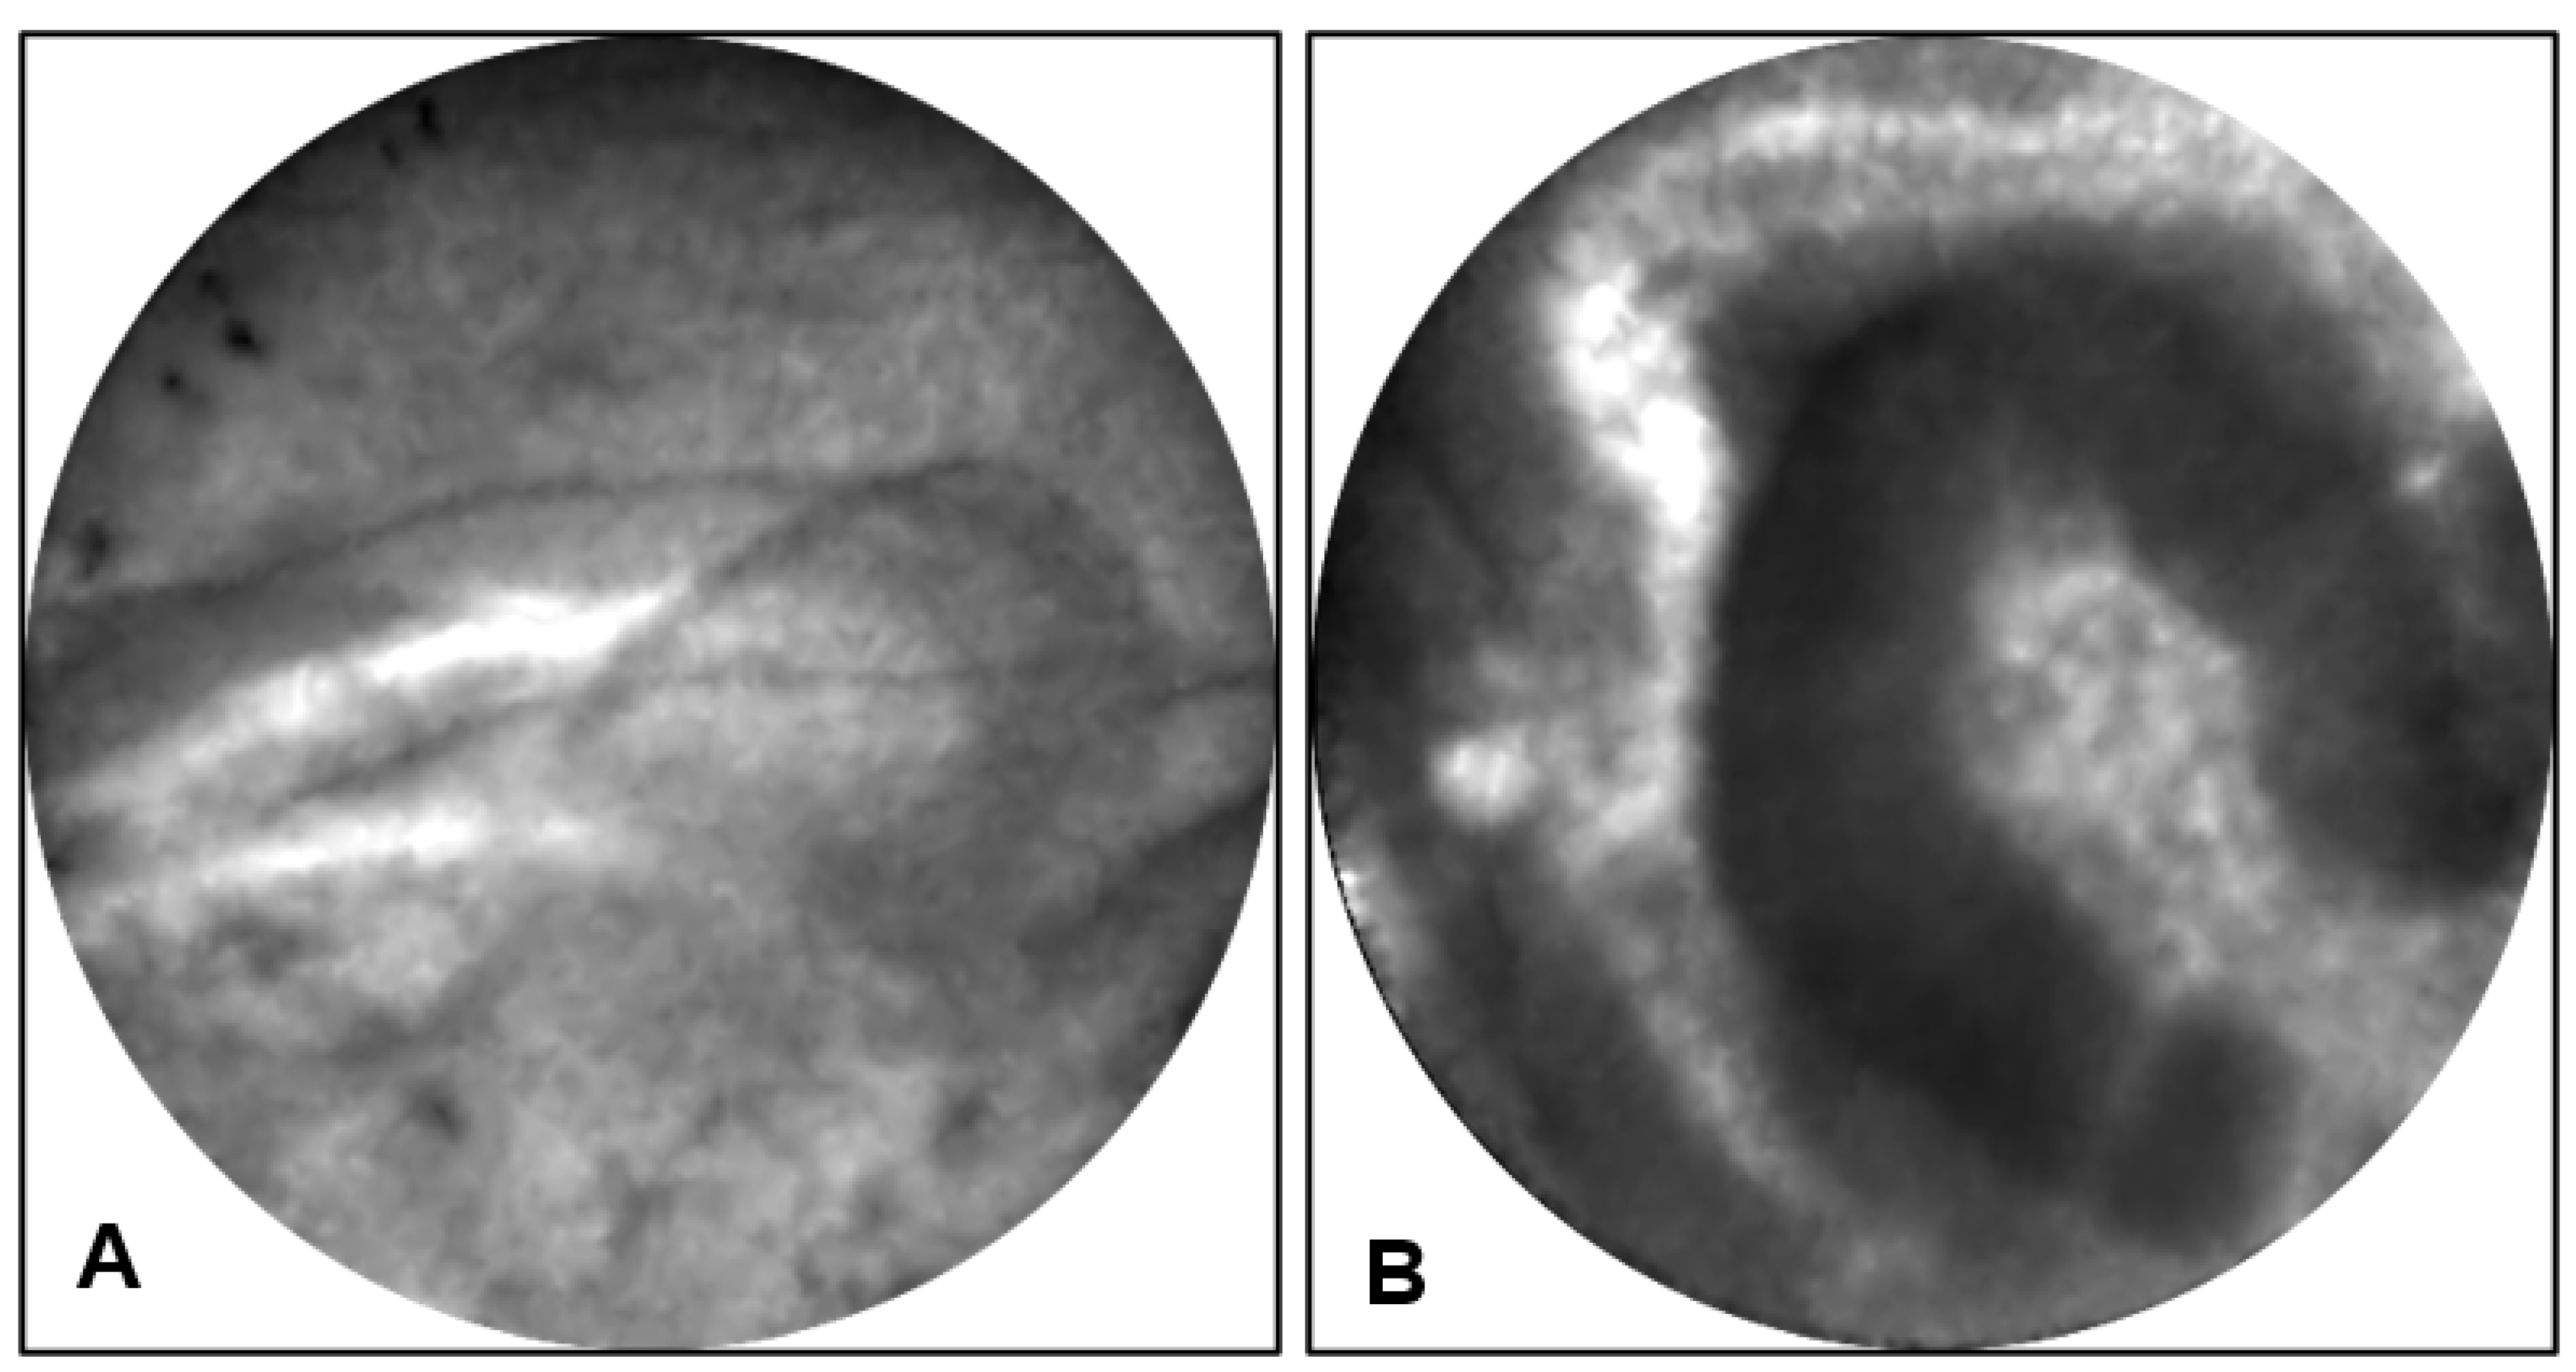

Endomicroscopy: EUS-nCLE of IPMN shows finger-like papillary projections composed of an outer epithelium and inner vascular core [23]. Figure 2 shows the typical appearance of IPMNs as seen during real-time in vivo EUS-nCLE procedure. Figure 2A shows a BD-IPMN with low-grade dysplasia. The epithelium is thinner and more translucent. Comparatively, Figure 2B demonstrates BD-IPMN with high-grade dysplasia with thicker and darker epithelium indicative of cellular and nuclear stratification, respectively. Both computer-aided artificial intelligence algorithms and human-interobserver studies have revealed a high diagnostic accuracy in nCLE-guided differentiation of IPMNs [24,25].

Figure 2.

(A) EUS-nCLE of BD-IPMN with papillae revealing thin translucent epithelium in a lesion with low-grade dysplasia. (B) BD-IPMN revealing large dominant papillary structure with a thick and dark epithelium in a lesion with high-grade dysplasia.